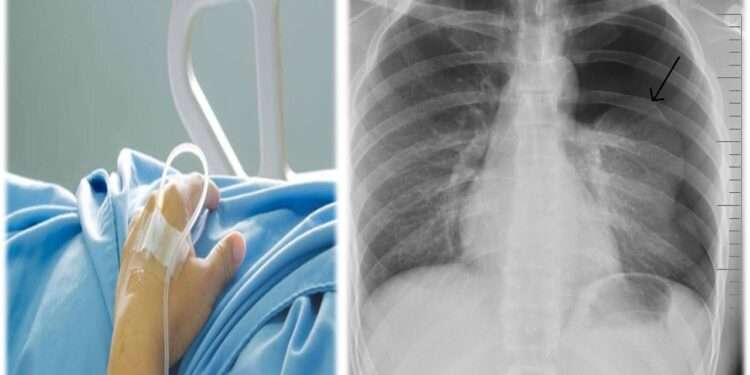

أكد مرافق نجل رئيس الوزراء الأسبق، أسعد سعد جمعة أن (جمعة الابن)، دخل في غيبوبة من جديد، دون أن يوضح تفاصيل. و لكن لاحقاً لعدد من المناشير، بدأها بـ(تم نقل اسعد سعد جمعه للمستشفى الآن إثر نزيف داخلي حاد، الرجاء الدعاء له بالشفاء العاجل، ليكمل في منشور آخر بعد دقائق: “يؤسفني اخباركم بأن قلب السيد أسعد توقف والأطباء يسعون لانعاشه كهربائياً.” ثم أخيراً في شرح حالته الصحية التي يُرثى لها قال: “الحمد والشكر لله، بدأ قلب اسعد سعد جمعه بالنبض ،ولكن تم كسر ضلعين لأنهم اضطروا لاستعمال ٤٥٠ ك جول. يذكر أن نجل رئيس الوزراء الأسبق، خرج في الكثير من المواقع الإلكترونية و المؤسسات الإعلامية، مشيراً أنها تعرض للظلم من أشخاص بعينهم، حرموه من ورثة والده، ألأمر الذي جعله حبيس المنزل للمطالبات المالية و حباس المستشفيات و أسرة (الـicu , ccu)..